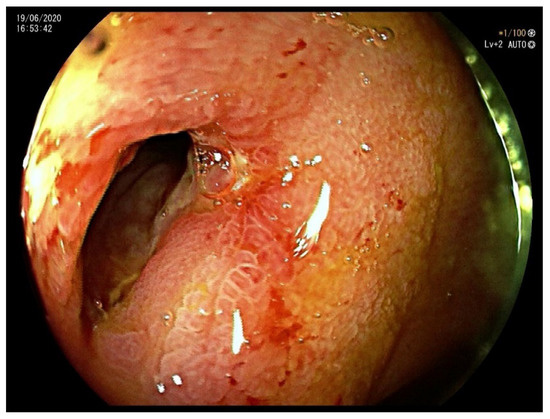

1.2. Case 2